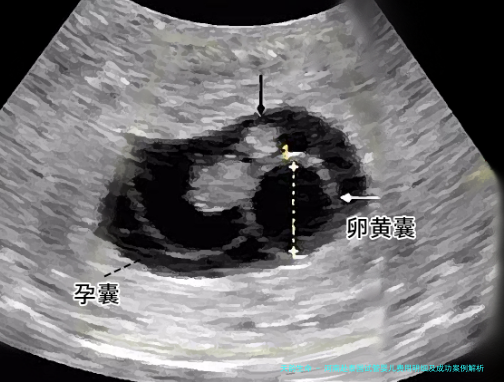

五月周期实例表现:例假第3天启用促排,十二日获卵八枚。显微受精技术受精7枚,养囊第五日存活4枚,经染色体筛选后优先选择2枚XY胚胎。移植后十二日HCG值达86五毫国际单位/毫升,成功创造妊娠。